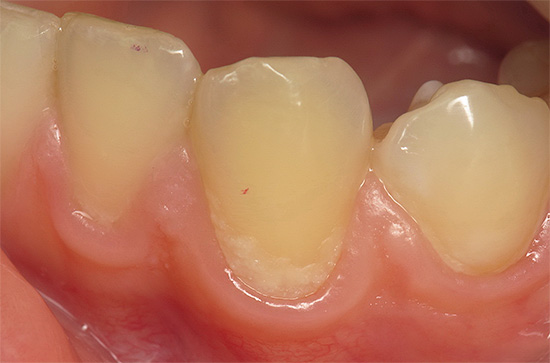

Abaixo está uma foto de cárie cervical no estágio local:

A maioria das pessoas com manchas de cárie nos dentes na região cervical (estágio inicial) já pode sentir desconforto: desconforto, dor e até certas dores características dos dentes hipersensíveis, mas isso é menos comum. Basicamente, a cárie no estágio de mancha é assintomática e é determinada apenas visualmente na forma de uma mancha branca ou pigmentada.